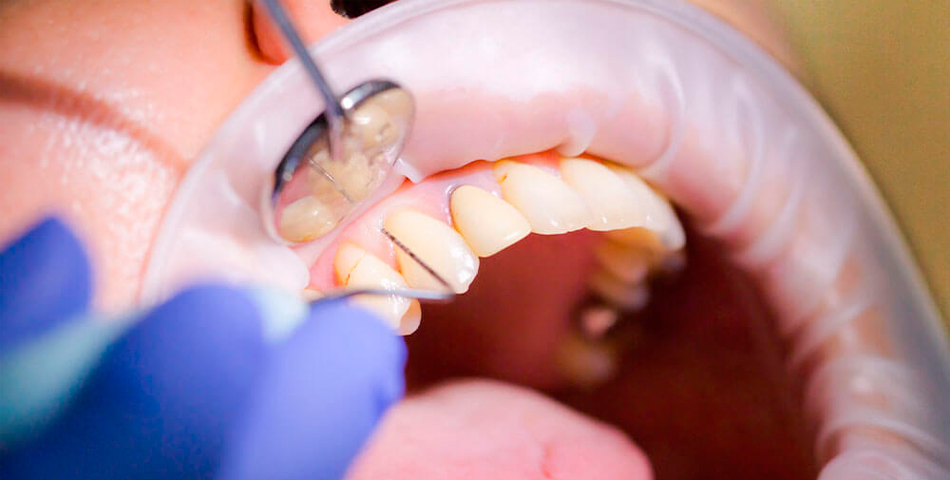

- Підготовка та анестезія. Для абсолютного комфорту пацієнта лікар проводить ефективне місцеве знеболювання. Після цього зуб ізолюється за допомогою кофердаму, щоб захистити робоче поле від потрапляння слини та бактерій.

Лікування кореневих каналів у нашій стоматології в Дніпрі виконується з використанням передових технологій. Ключовим інструментом є дентальний мікроскоп. Він забезпечує багаторазове збільшення операційного поля, що дозволяє лікарю:

- Чітко бачити анатомічні особливості та додаткові канали.

- Реально видалити всі уражені тканини.

- Провести максимально щільне та точне пломбування.

Це значно підвищує успішність лікування навіть найскладніших випадків періодонтиту.